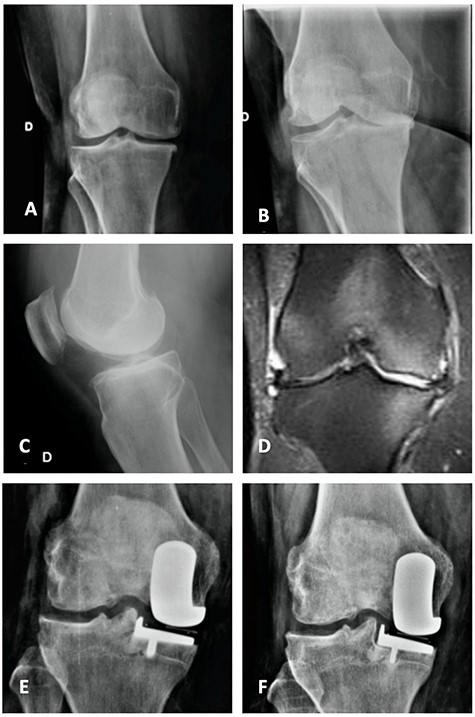

Coronal (A) and sagittal (B) T2 MRI—left knee—showing severe MP SIFK; Anterior (C) and lateral view (D) X-ray images of immediate postoperative period (medial UKA); Anterior (E) and lateral view (F) X-ray images with 3 months of follow-up with tibial component loosening.

Orthostatic anterior view (A) and Rosenberg (B) X-ray images with medial osteoarthritis—right knee; Lateral view X-ray image of the same knee (C); T2 coronal MRI (D) with severe MP and femoral condyle SIFK; Immediate postoperative X-ray image (E) and 3 months after surgery (F) showing tibial component loosening.